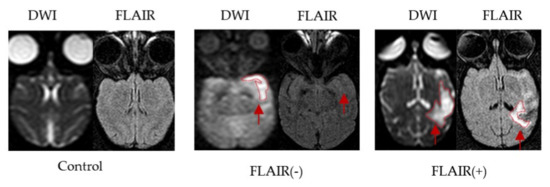

2.2.3. MRI Analysis

3.1. General Results of the Stroke Model and MRI Assessment